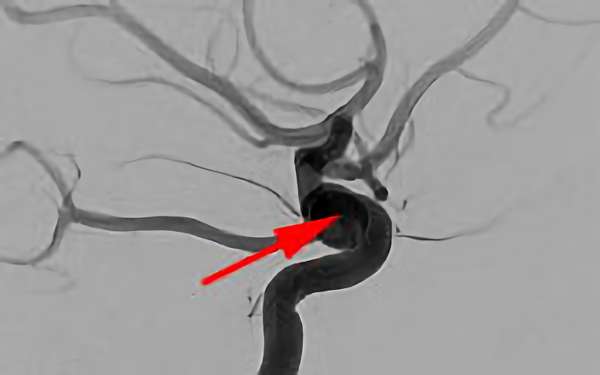

症例 '20年2月

No.

757

'20年2月10日

くも膜下出血

50代

兵庫県の病院

手術写真

治療

前

中

後

手術日